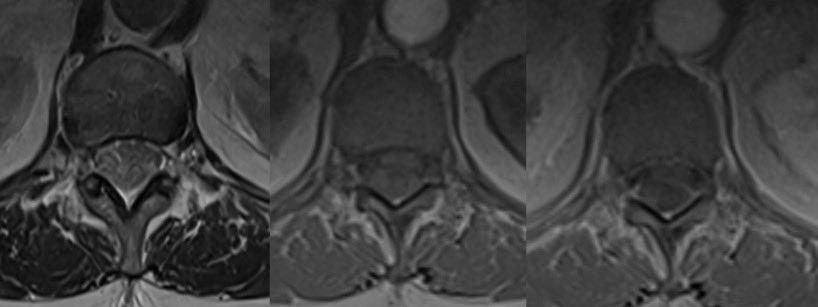

⭐️ Answer: Spontaneous spinal epidural hematoma (no clear risk factor in this case)